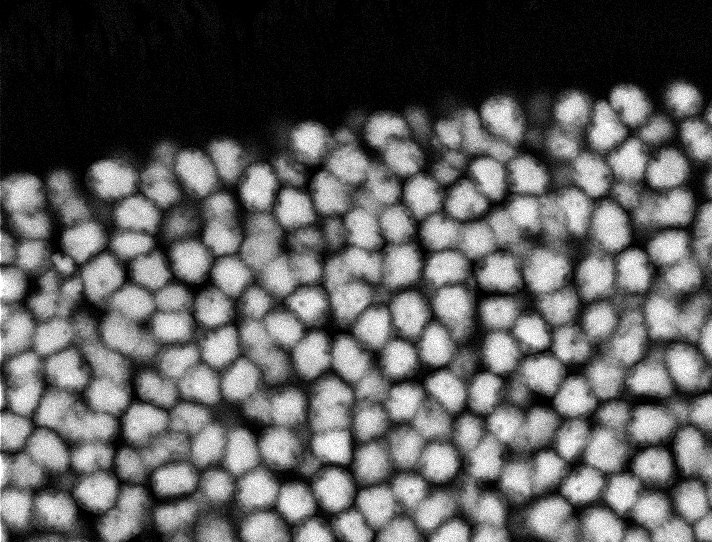

Nuclei